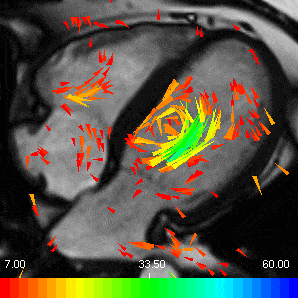

Blood flow in the heart

The heart squeezes the blood into the whole body. At rest, the heart pumps 5 litres of blood per minute. However, at peak exercise, it can pump up to 20 litres of blood per minute!